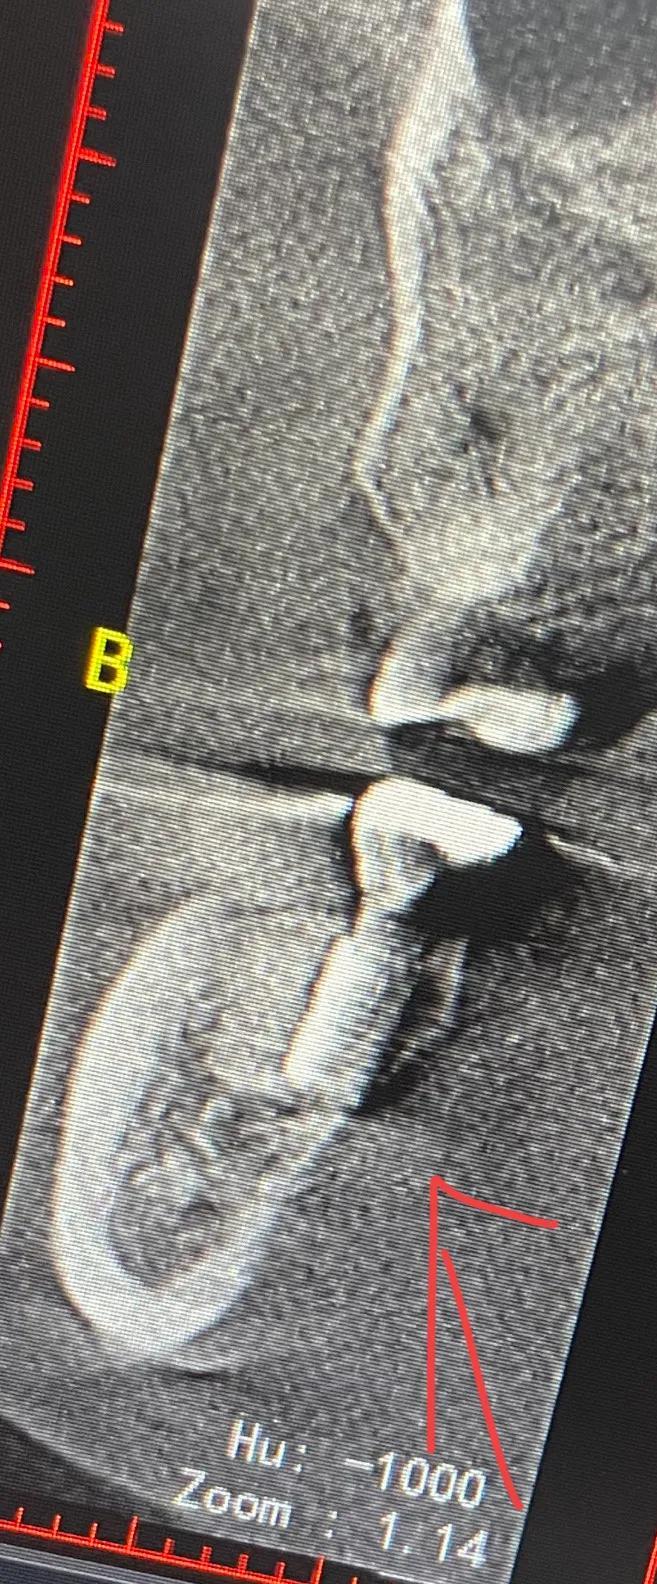

幾天后醫(yī)生?說(shuō)把牙冠拿下來(lái)從新做 在那么劇烈的疼痛下 但凡醫(yī)生能早點(diǎn)?找一下原因 也不會(huì)遭這么大的罪 去其他醫(yī)院拍片子 說(shuō)是?有骨頭高于種植體

戴上牙冠 多出來(lái)的骨頭在牙冠和種植體中間擠壓 所以會(huì)疼

沒(méi)辦法自己又出去拍片子 找原因 看了幾家醫(yī)院 才知道連種植體也種偏了 牙冠也沒(méi)有就位………